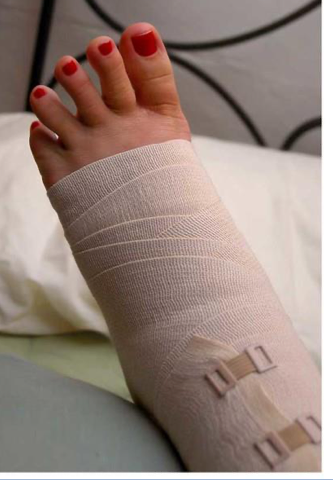

<p>what is the name, type, and purpose of this orthotic </p>

what is the name, type, and purpose of this orthotic

name: ace wrap

type: soft

purpose: controls swelling and pain (provides no stability)